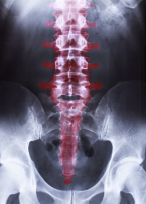

허리 척추협착증은 허리 부근 척추 채널이 좁아져서 척추 신경이 압박을 받아 발생하는 질환입니다. 이러한 채널의 좁아짐은 여러 가지 원인에 의해 발생할 수 있습니다.

첫째, 나이가 들면서 척추가 노화되고 디스크가 변성되면 척추 채널이 좁아지게 됩니다. 이는 척추 채널의 골절, 척추 관절염, 척추 전방 전위증 등과 같은 이상으로 더욱 심화됩니다.

둘째, 디스크의 병변은 척추 채널의 좁아짐을 유발합니다. 디스크가 미세하게 파열되면 디스크의 내용물이 밖으로 새어나와 주변 조직을 압박할 수 있습니다. 이러한 디스크 병변은 척추 채널의 좁아짐을 유발하고 이로 인해 신경이 압박됩니다.

셋째, 척추 골절은 척추 채널의 크기를 감소시키고 신경 압박을 유발할 수 있습니다. 척추 골절은 골절 후에 척추의 압축성 증가, 이상적인 자세의 유지 어려움 등으로 척추 채널의 크기를 감소시킵니다.

넷째, 척추 전방 전위증은 척추의 일부가 전방으로 움직임으로 인해 척추 채널이 좁아지는 현상입니다. 이는 척추의 미세한 파열로 인한 디스크의 이탈, 나이로 인한 디스크의 노화 등으로 인해 발생할 수 있습니다.

다섯째, 척추 관절염은 척추의 관절이 염증을 일으켜서 척추 채널이 좁아지는 경우가 있습니다. 척추 관절염은 대개 나이가 들면서 발생하며, 고형 관절염, 류마티스 관절염 등의 질환으로 인해 발생할 수 있습니다.

허리 척추협착증은 위와 같은 다양한 원인으로 인해 발생할 수 있습니다. 따라서, 원인에 따라 적절한 치료 방법을 선택해야 하며, 그에 따라 예방 및 관리 방법을 잘 생각해보아야 합니다.